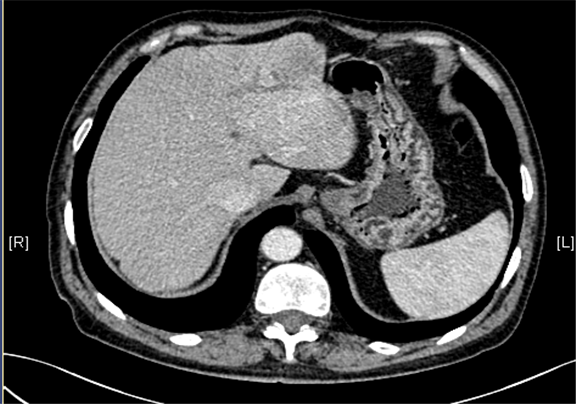

术前CT检查:

静脉期

下腹部增强CT示:肝左外叶占位,考虑恶性肿瘤伴门脉侵犯可能性大,符合肝硬化表现。

现病史:患者5月前因“肝硬化”行上腹部CT发现肝占位性病变(未见报告),建议随访观察,患者无乏力、恶心、呕吐、腹胀、腹泻、血便、食欲减退,无寒战,无头痛头晕,无皮肤粘膜黄染,无尿频、尿急、尿痛、血尿。3天前再行上腹部增强CT检查示:肝左外叶占位,考虑恶性肿瘤伴门脉侵犯可能性大,建议MR平扫+强化符合肝硬化表现。双肾多发小囊肿可能性大